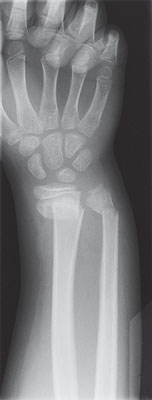

| X-ray of a broken wrist |